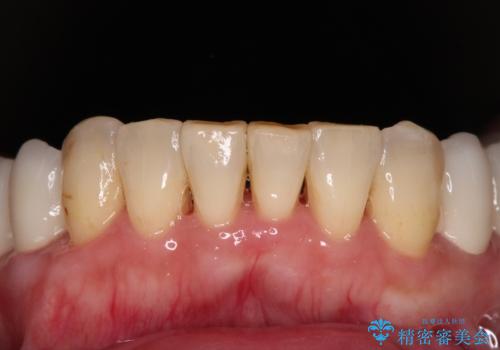

歯肉の状態が落ち着いた後に下顎の矯正治療を行い、その後補綴治療を行うこととしました。

油断をするとすぐに汚れが溜まって歯肉が腫れてきてしまうため、今後も定期的なメインテナンスが重要となります。